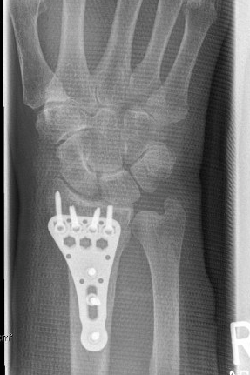

- Brüche (Frakturen) des Handgelenks, der Handwurzelknochen, der Mittelhand und der Finger